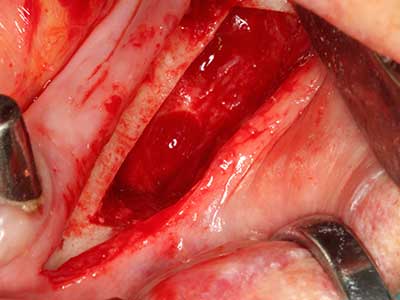

Sollen chirurgische Eingriffe mit unmittelbarer Knochenbeziehung an empfindlichen Strukturen wie Blutgefäßen oder Nerven erfolgen, so bergen rotierende Instrumente ein erhebliches Potential an iatrogener Schädigung. Gerade bei Nervdarstellungen nach iatrogener Schädigung, oder aber im Zuge einer Nervlateralisation für resektive und rekonstruktive Eingriffe oder Implantatinsertionen können piezoelektronische Geräte hilfreich sein Knochendeckel zu präparieren und nervnahe Hartgewebsanteile zu entfernen (Abb. 17-20). Ein leichter Kontakt des Nervstrangs zur Piezospitze bleibt dabei in der Regel folgenlos – allerdings kann eine unvorsichtige Vorgehensweise mit sägeartigen Bewegungen bzw. Ansätzen bei noch vorhandener knöcherner Unterlage durchaus temporäre oder aber auch permanente Nervschädigungen verursachen. Das Risiko einer solchen Schädigung wird jedoch als wesentliche geringer eingeschätzt als unter Anwendung von Säge- oder Fräsinstrumenten (Pereira, Gealh et al. 2014).

Abb. 18: Präparation eines Kortikalis-Deckels mit der Piezo-Knochensäge (Piezomed, W&H).

Abb. 19: Operationssitus nach Neurolyse und Osteomentfernung.